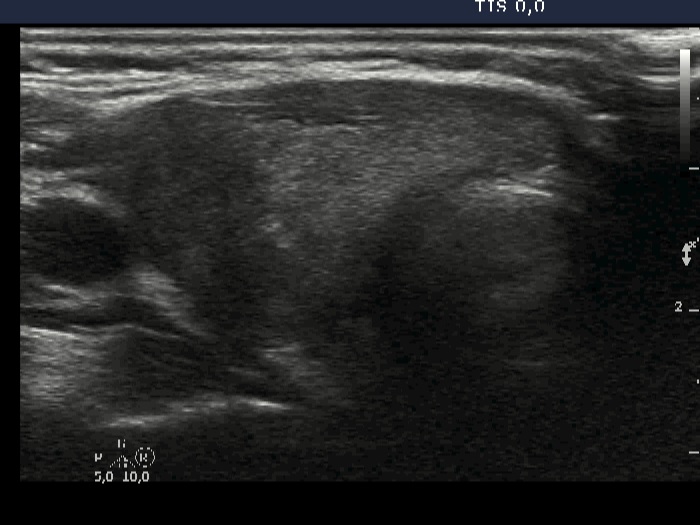

Ultrasonography: The thyroid was echonormal. There were multiple hypoechogenic areas with ill-defined borders in both lobes. According to the hypoechogenic areas, the vascularization was decreased.

The first two images at the first exam illustrate why video is better than still image. You can extract an image from the video at almost any time that not characteristic of the particular thyroid or, as in this case, misleading. Watching the video, it is clear that the hypoechogenic parts have fundamentally blurred borders. The real situation is represented by the first image. But the second does not show just that. Here, the nodule appears to have a sharp, lobulated margin.

If we look only at the ultrasound image, we may have doubts about whether it is a discrete lesion of thyroiditis or a real nodule. However, considering the clinical data, it is clear that this is an active focus of subacute thyroiditis and not a true nodule.